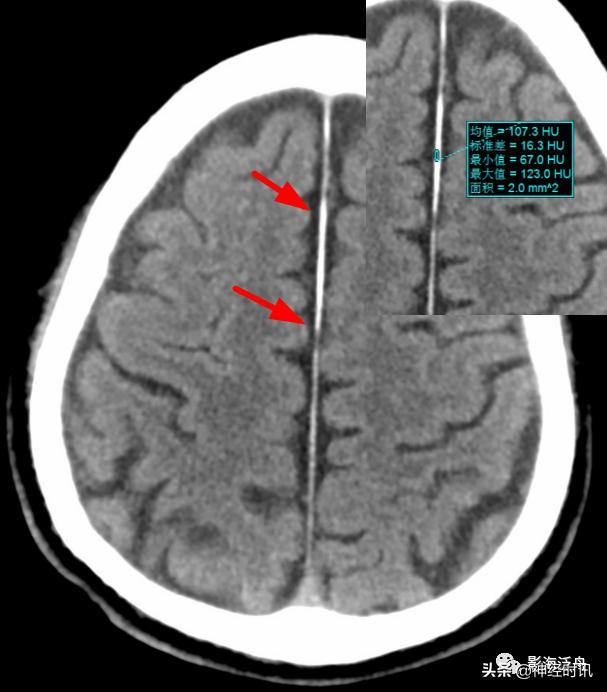

国内一些文献将大脑镰一侧不对称的高密度影被定义为“偏密征”,并认为上述影像学特征是诊断大脑镰旁少量蛛网膜下腔出血的可靠征象,可提示出血部位位于“偏密征”附近,或继发于邻近的其它颅内损伤。

本例颅脑外伤患者的大脑镰右旁可见“偏密征”,但这个血肿的边缘非常光滑(红箭)且未延伸至邻近脑沟内,边缘似乎还带有一些张力感,笔者觉得此例诊断为大脑镰旁硬膜下血肿更合适。但不管怎么说,“偏密征”用于鉴别是否存在局限性的脑外伤还是很有用的。